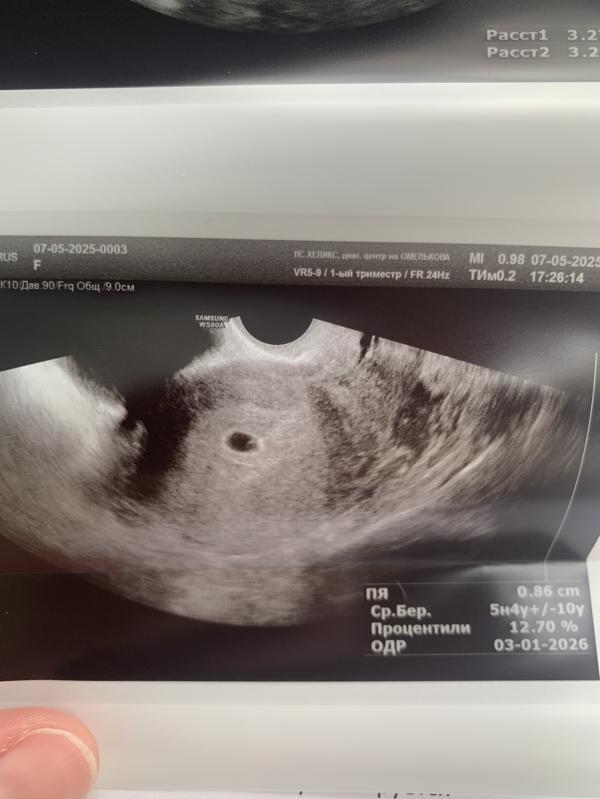

Попала я на УЗИ!

С беременностью все хорошо, соответствует сроку и нет никаких отслоек.